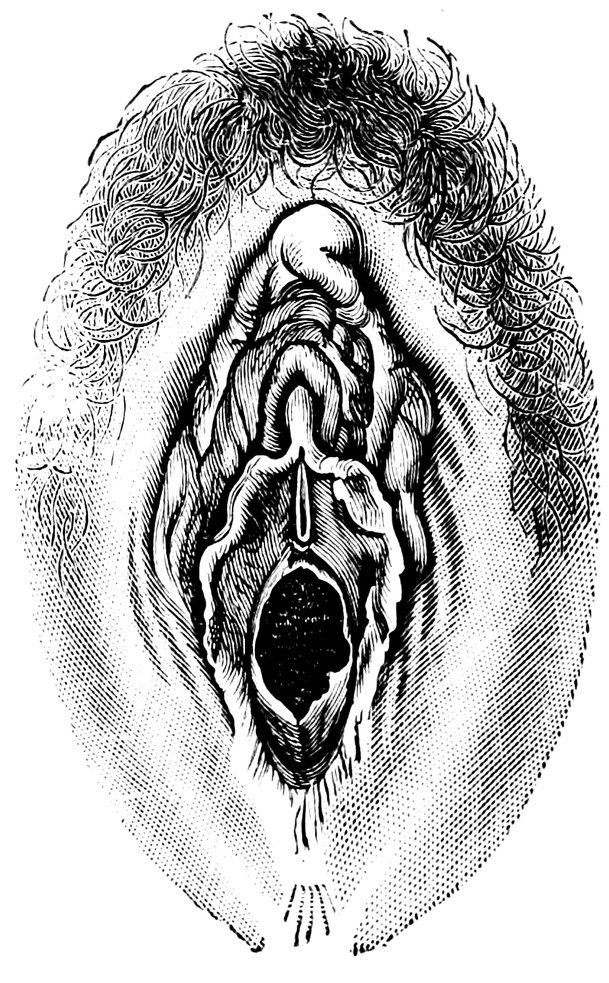

| 12. | Female external genital organs of a virgin | 54 |

| 13. | The external genital organs of a virgin | 55 |

| 48. | The female pudendum, or vulva, with the labia majora | 204 |

| 49. | Vestibule of the vagina, with the labia minora or nymphæ, etc | 205 |